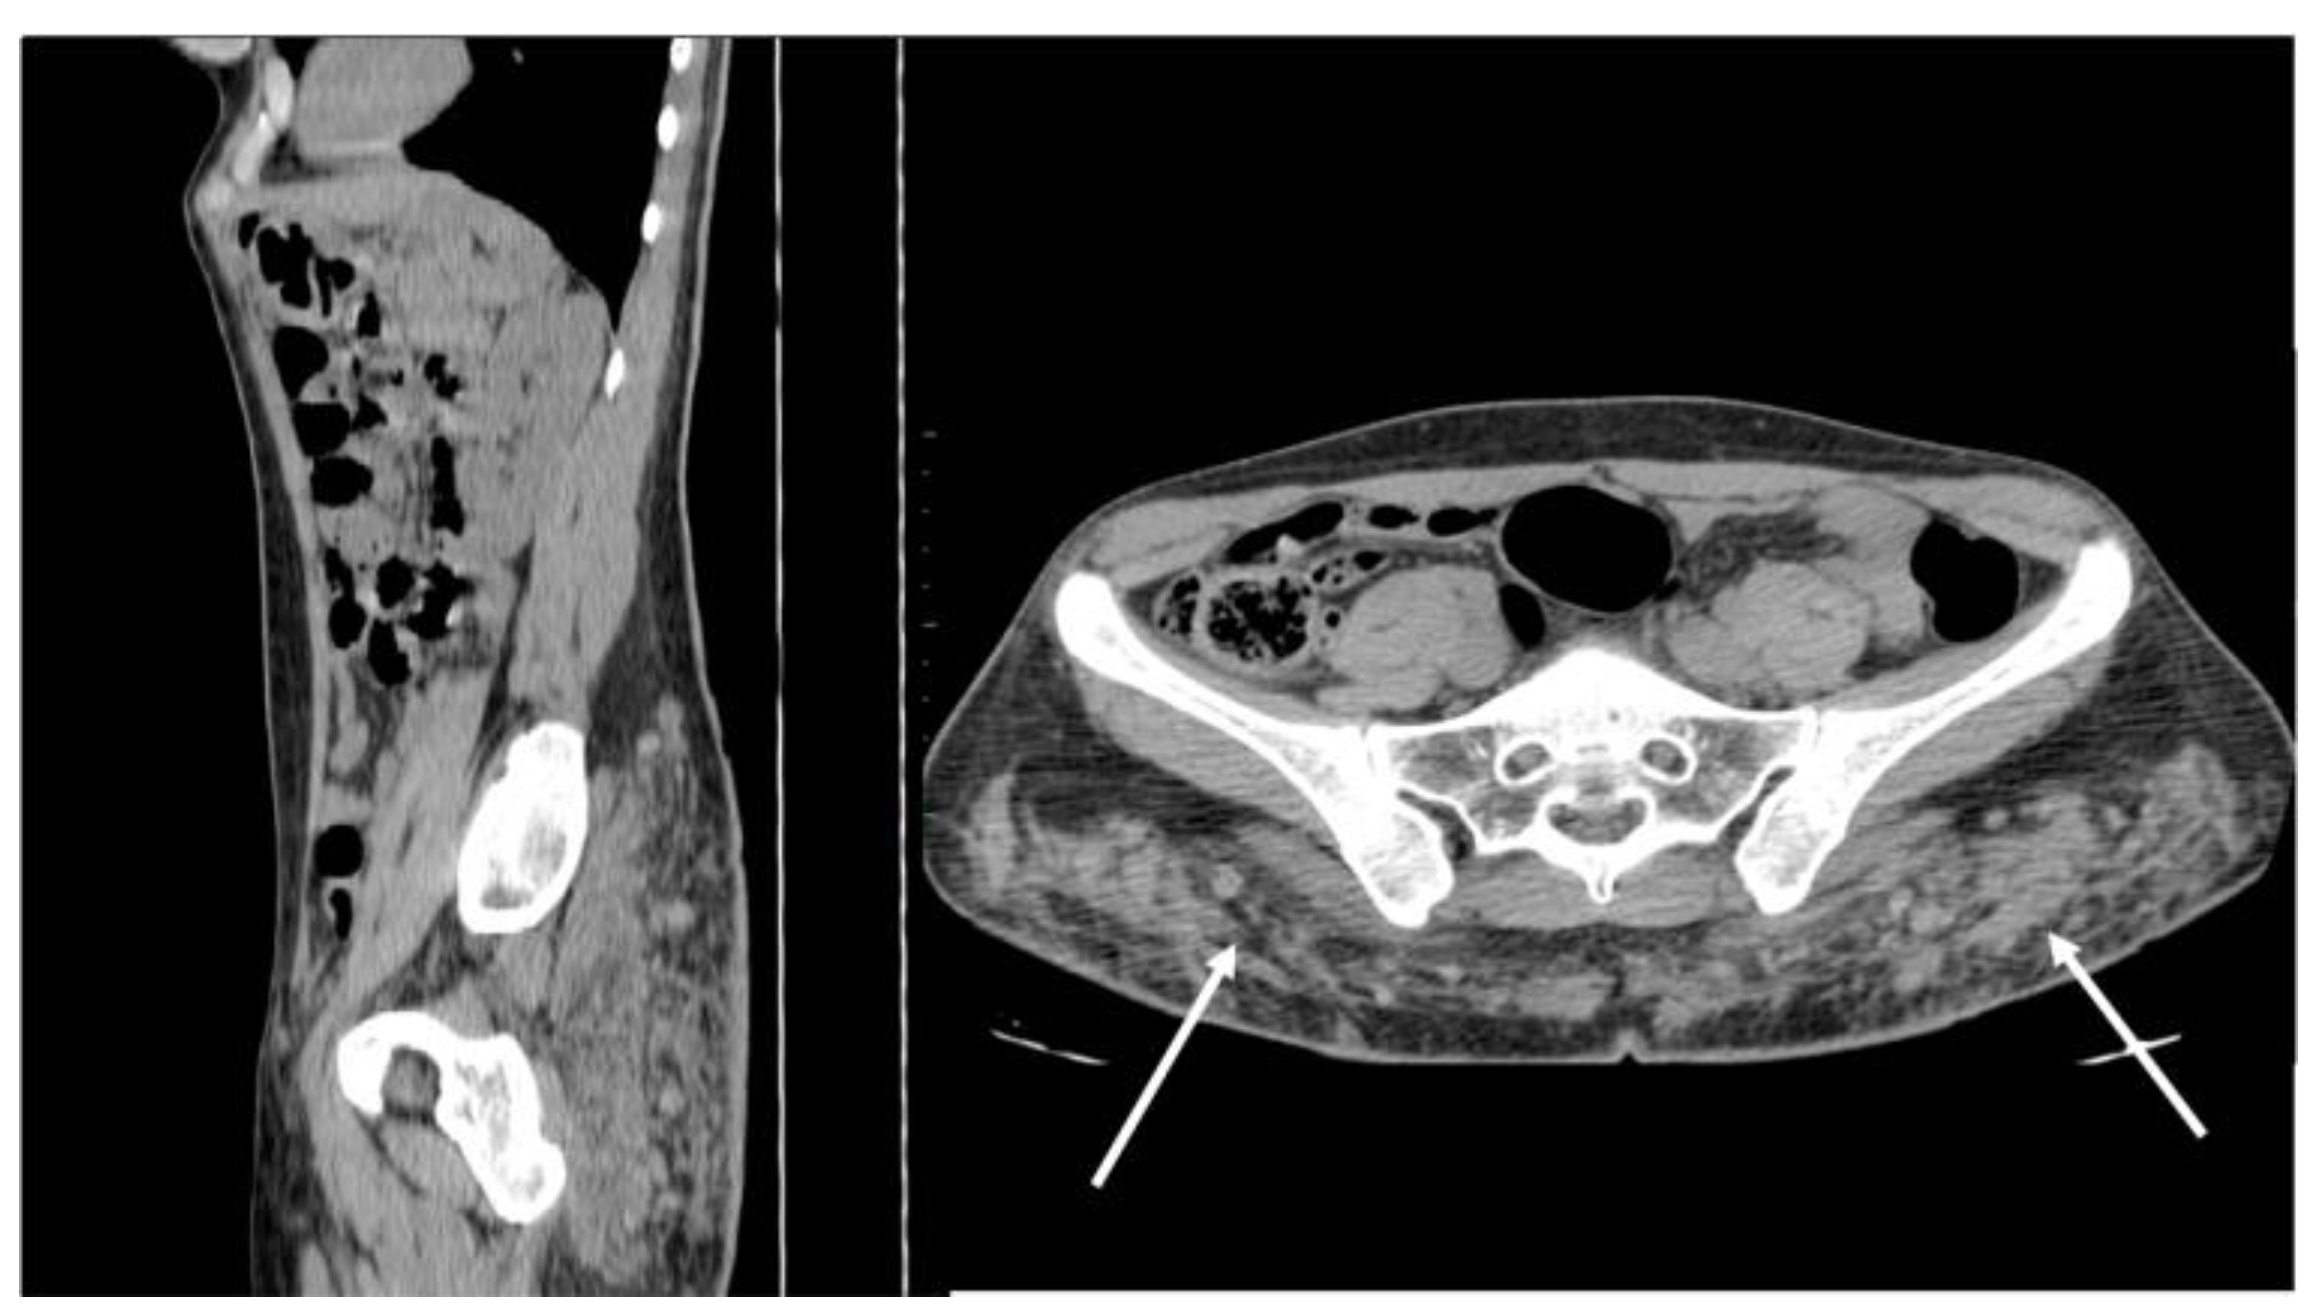

5.5. Splenosis